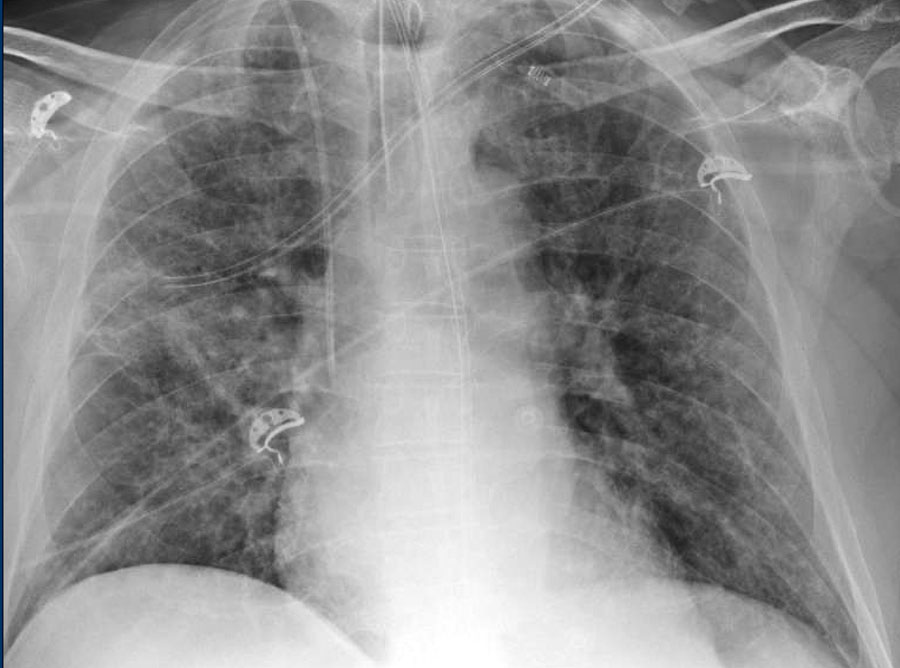

Covid Normal Man Chest X Ray

Covid Normal Man Chest X Ray. In our experience, baseline cxr had a sensitivity of 68.1%. Findings and correlation with clinical outcome. This guideline serves to both help identify which radiographic findings are most likely due to covid 19 chest involvement and which findings should prompt consideration of …